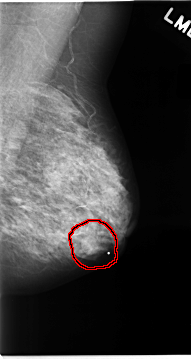

FILE: C_0064_1.RIGHT_MLO.OVERLAY

TOTAL_ABNORMALITIES 1

ABNORMALITY 1

LESION_TYPE CALCIFICATION TYPE AMORPHOUS DISTRIBUTION CLUSTERED

LESION_TYPE MASS SHAPE IRREGULAR MARGINS SPICULATED

ASSESSMENT 5

SUBTLETY 5

PATHOLOGY MALIGNANT

TOTAL_OUTLINES 1

BOUNDARY